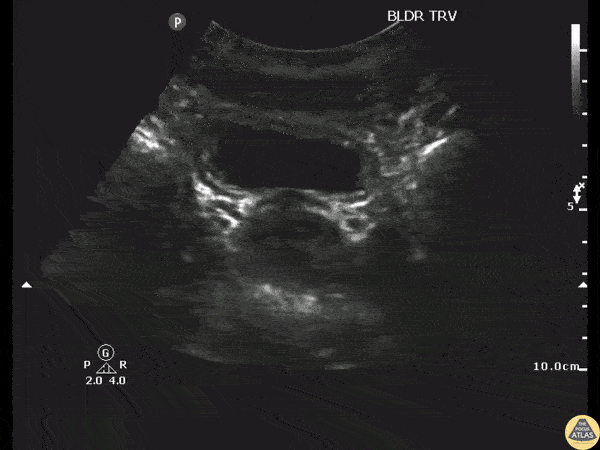

Renal/GU - UVJ Stone

Patient with flank pain was found to have a 3mm unilateral obstructing ureteric stone without hydronephrosis. Image courtesy of Robert Jones DO, FACEP @RJonesSonoEM Director, Emergency Ultrasound; MetroHealth Medical Center; Professor, Case Western Reserve Medical School, Cleveland, OH View his original post here